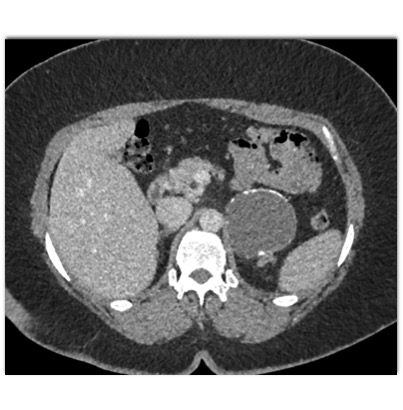

The most likely diagnosis in this case is

adrenal myelolipoma

old adrenal hematoma

pancreatic pseudocyst

adrenal carcinoma